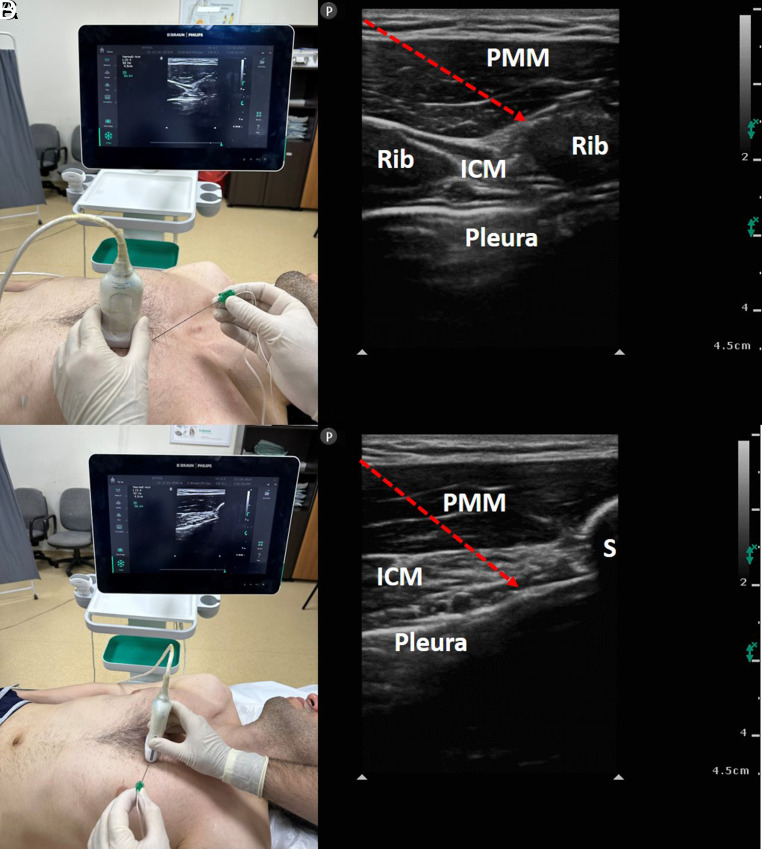

The sine qua non of enhanced recovery after surgery protocols designed to improve the perioperative experiences and outcomes of patients is to determine the most appropriate analgesia management. Although many regional techniques have been tried over the years in this purpose, interfacial plane blocks have become more popular with the introduction of ultrasound technology into daily practice and they have great potential to support effective postoperative pain management in many surgeries. The current article focuses on the benefits, techniques, indications, and complications of interfascial plane blocks applied in cardiac, abdominal, and spine surgeries.